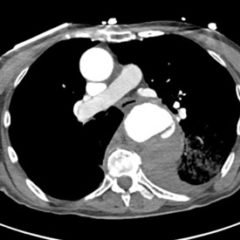

A 52-year-old male presented to the emergency room with left chest wall pain and upper back pain after falling from an estimated height of 24 feet, landing on his back. On physical exam, the patient had crepitus to left chest wall and back and was persistently hypotensive in the trauma bay.

Plain film anteroposterior (AP) radiography of the chest shows left-sided subcutaneous emphysema (red arrow) with overlapping muscle striations of the pectoralis major (green arrow). After chest tube placement (blue arrow), AP chest radiography shows persistent left-sided subcutaneous emphysema (red arrow). CT of the chest shows pneumomediastinum (blue arrow), left apical pneumothorax (pink arrow), and subcutaneous emphysema (red arrow) at the level of T2. At the level of T6, rib fractures can be visualized on the CT (yellow arrow). At the level of T8, left sided pneumothorax is also seen (pink arrow) as the absence of lung tissue on CT.

Injuries of the thorax account for 25% of all mortality in trauma patients, of which many are preventable deaths by simple interventions.1,2 One sign commonly seen in patients with chest trauma is subcutaneous emphysema. The presence of this underlying emphysema has been suggested to be a sign of injury to the respiratory tract, making it clinically significant.3,4 Specifically, subcutaneous emphysema has been shown to be a clinical predictor of occult pneumothorax, with an odds ratio of 5.47.3 Furthermore, these injuries to the respiratory tract (pneumothorax /hemothorax, pneumomediastinum, etc.) can lead to hemodynamic instability and respiratory failure.4-6

Treatment of these injuries consist of different measures. Subcutaneous emphysema does not usually require treatment and will reabsorb spontaneously.7 Pneumothorax and hemothorax are both treated with chest tube placement. In a hemothorax, however, if the tube evacuates more than 1,500 mL of blood immediately or more than 200 mL/hour, the patient should be taken to the operating room for surgical exploration of the chest.8 Therefore, complete investigation into the underlying cause of subcutaneous emphysema is essential in managing patients with chest trauma.

In this patient, given the findings of multiple bilateral rib fractures, bilateral hemothorax/pneumothorax and multiple spine fractures, bilateral chest tubes were placed which had immediate output. The patient was admitted to surgical intensive care unit for chest tube management, pulmonary hygiene and further management of his other injuries.